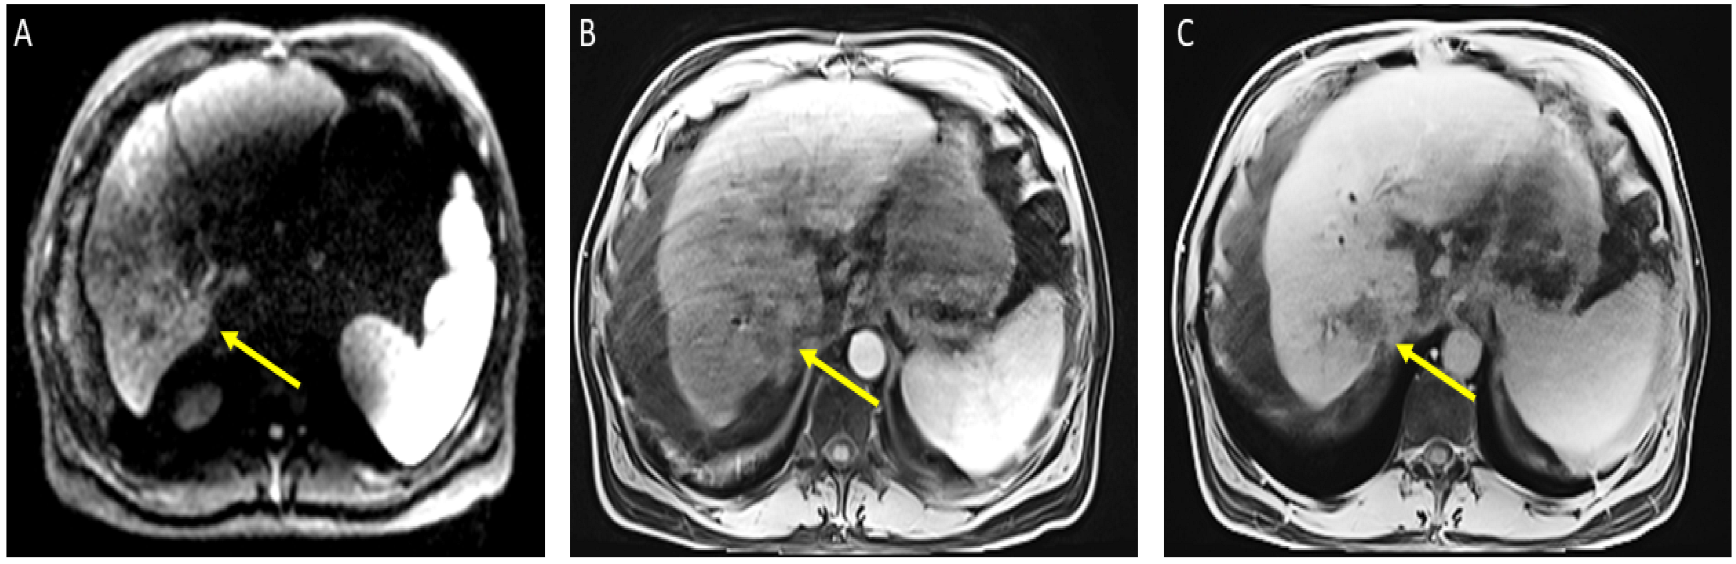

The patient received a total of 6 cycles of atezolizumab 1200 mg intravenously plus a total of 5 cycles of bevacizumab 15 mg/kg (missed one cycle of bevacizumab) given on day 1 of a 21-day cycle. Therapy was then held for two months prior to evaluation for OLT. Follow-up MRI 8 weeks after treatment showed a significant interval treatment response with shrinkage of the segment 7 tumor, as seen in Figure 2. Additional imaging follow-up at 6 months showed post-treatment atrophy of the right lobe of the liver, stable non-enhancing segment 7 mass (LR-TR non-viable); with a new 8 mm lesion in segment 2 of the liver (LI-RADS 4 for arterial enhancement, washout, and size less than 10 mm), as can be seen in Figure 3. PET/CT scan showed no metabolic uptake in the right hepatic lobe with suspected inflammatory uptake in the common bile duct. No bone metastases were appreciated in the bone scan.

Figure 2.

Magnetic resonance imaging of the abdomen. Cirrhosis, splenomegaly, and ascites were noted. Significant interval treatment response. Segment 7 mass has decreased in size (now 3.3 × 3 cm). (A) Diffusion-weighted imaging (DWI): decreased diffusion restriction of seg 7 mass; (B) (arterial)/(C) (delayed) T1 post-contrast imaging: mass is now hypovascular (captured at the follow-up visit, and 8 weeks after the atezolizumab plus bevacizumab started).